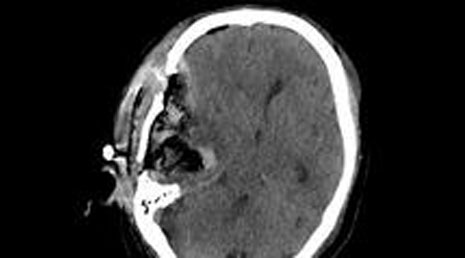

54. Sphenoidal wing meningioma